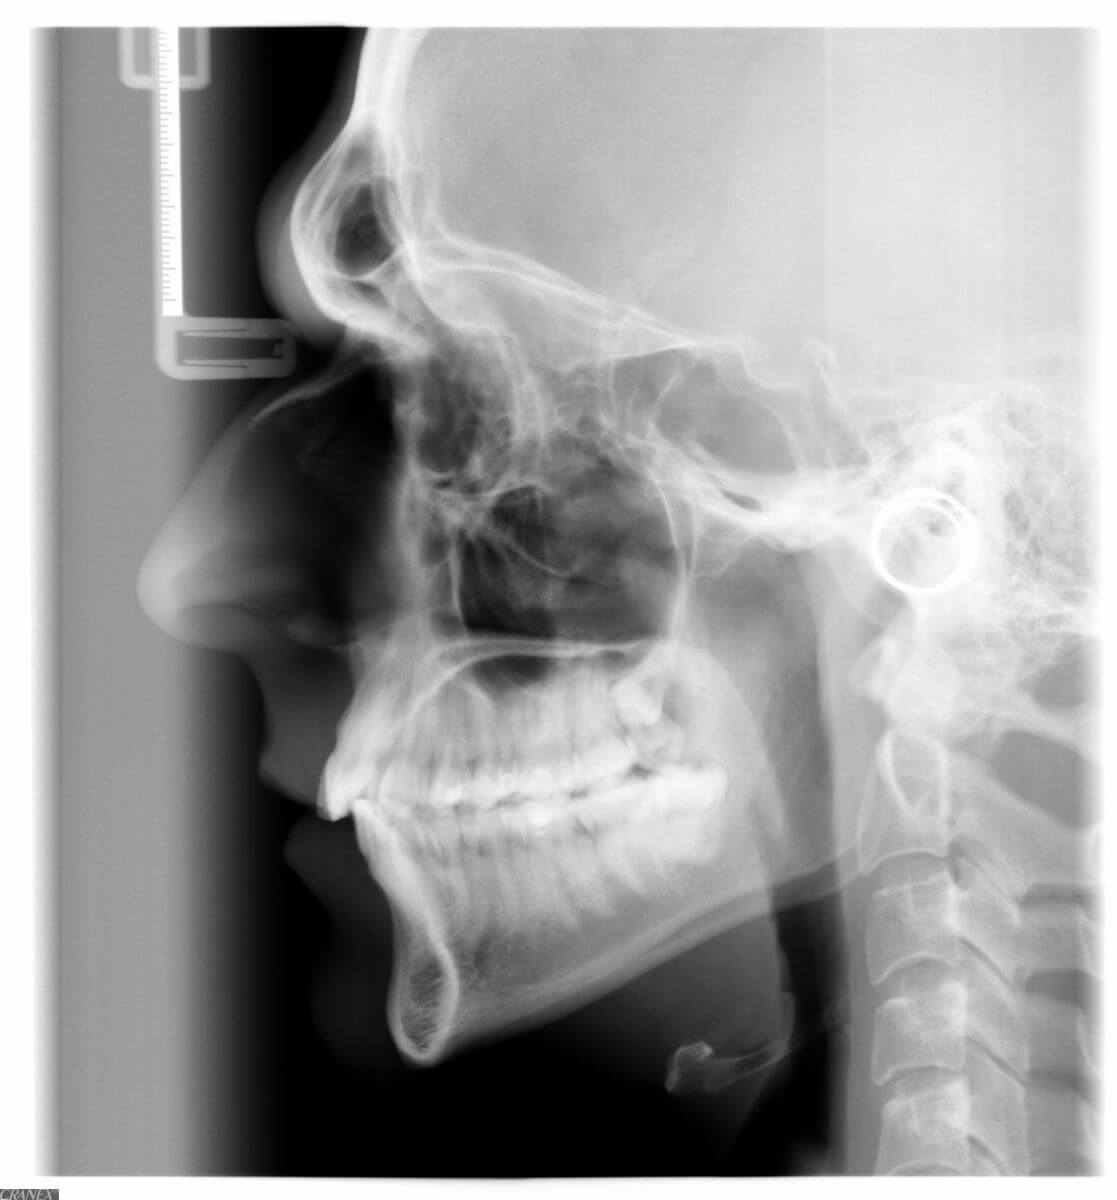

Что из себя представляет рентгеновский снимок черепа в боковой проекции?

Külgülesvõtte röntgenpilt